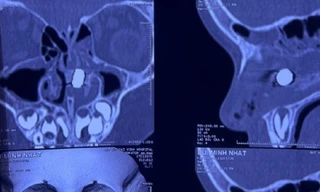

TPO - Bị hàng xóm dùng đũa tấn công, người đàn ông nhập viện trong tình trạng dị vật xuyên từ hốc mắt phải sang hốc mũi trái, nguy cơ thủng nhãn cầu. Ca phẫu thuật cứu bệnh nhân được các bác sĩ của Bệnh viện Mắt TPHCM và Bệnh viện Tai Mũi Họng khẩn trương thực hiện.